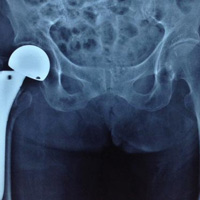

Hình chụp X-quang cho thấy cụ Th. bị gãy liên mấu chuyển xương đùi.

Các bác sĩ quyết định phẫu thuật thay khớp háng bán phần (bipolar) có xi măng, với stemp cán dài cho cụ Th. Ca phẫu thuật kéo dài 55 phút. Một ngày sau mổ, cụ đã ngồi dậy ăn uống, tập vận động phục hồi chức năng. Bệnh nhân đã tập đi lại và xuất viện sau 10 ngày điều trị.